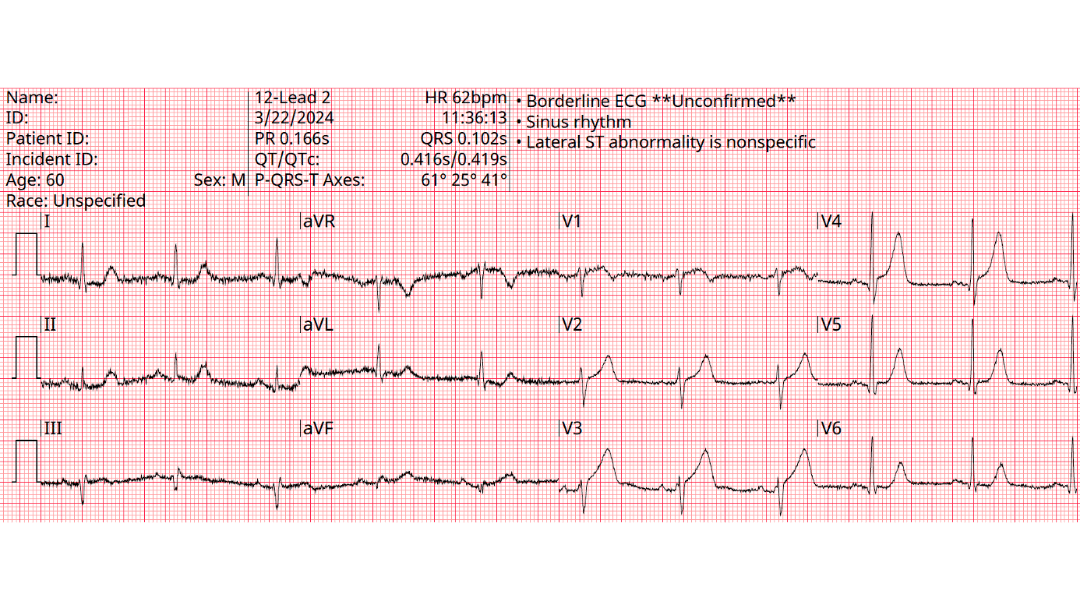

A 68 yo man is brought to the emergency department by EMS with acute chest discomfort. The following prehospital ECG was obtained and shows concave ST elevation across multiple leads. The computer interprets the tracing as benign early repolarization.....ecgweekly.com/weekly-workout…